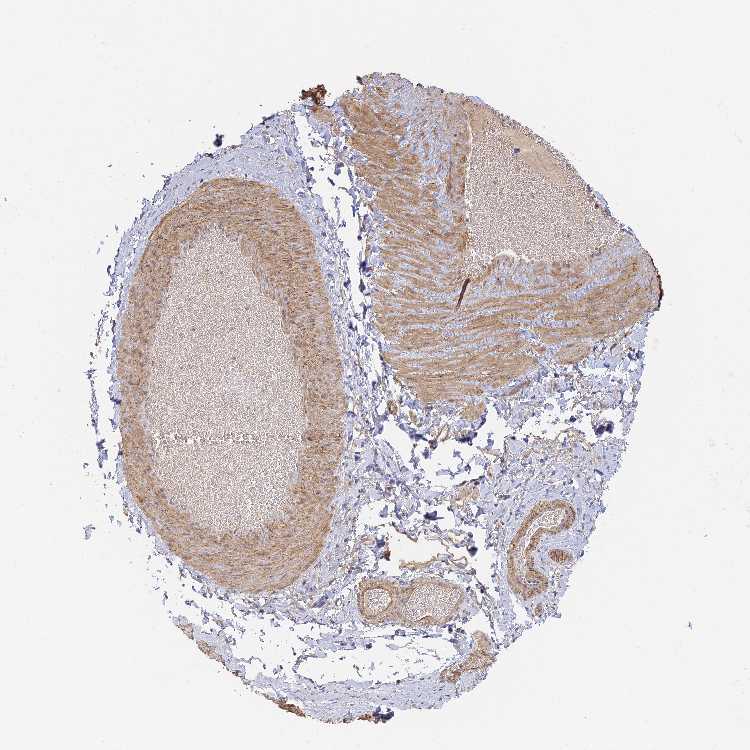

ADIPOSE TISSUE - Antibody stainingi

Antibody staining in the annotated cell types in the current human tissue is reported as not detected, low, medium, or high, based on conventional immunohistochemistry profiling in selected tissues. This score is based on the combination of the staining intensity and fraction of stained cells.

Each image is clickable and will lead to virtual microscopy that enables deeper exploration of all samples and also displays staining intensity scores, fraction scores and subcellular localization as well as patient and tissue information for each sample.

Antibody HPA044425

Adipocytes Low